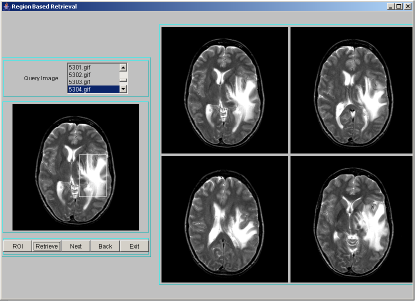

A data structure based on hashing technique is used to store all images along with the texture feature data. A combined index is adopted to point to all similar images in terms of the texture features. When a query is made based on an example image, the example image is processed for index value. Only those images that are in the same hash bucket as those of the queried image are compared for similarity. For each image in the database, segmentation procedure discussed in section 2 is applied to identify region-of-interest and describe segmented region by texture features: entropy, energy and contrast. The texture features extracted are quantized to integer values between 0 to 9. The combined index of these features is: , where [ ] represents quantization. Each combined index stores feature data along with the image object. For a query image, after finding the region-of-interest, the above mentioned texture features have to be computed, quantized and the combined index derived. Only those images that are stored at the combined index matching those of the query index, are extracted as resultant target images for a given query image. These resultant images are sorted using Euclidean distance measure in the decreasing order of similarity against the query image and displayed four images at a time using JAVA-AWT based GUI. A few representative snapshots of region-based indexing and retrieval are shown in Figure 1. Hash table offers very fast insertion and searching. Irrespective of the size of the data, insertion and searching can take close to constant time . Not only are they fast, hash tables are simple and easy to implement. Searching using hash tables are significantly faster than using tree, which operate in time.

![]() |